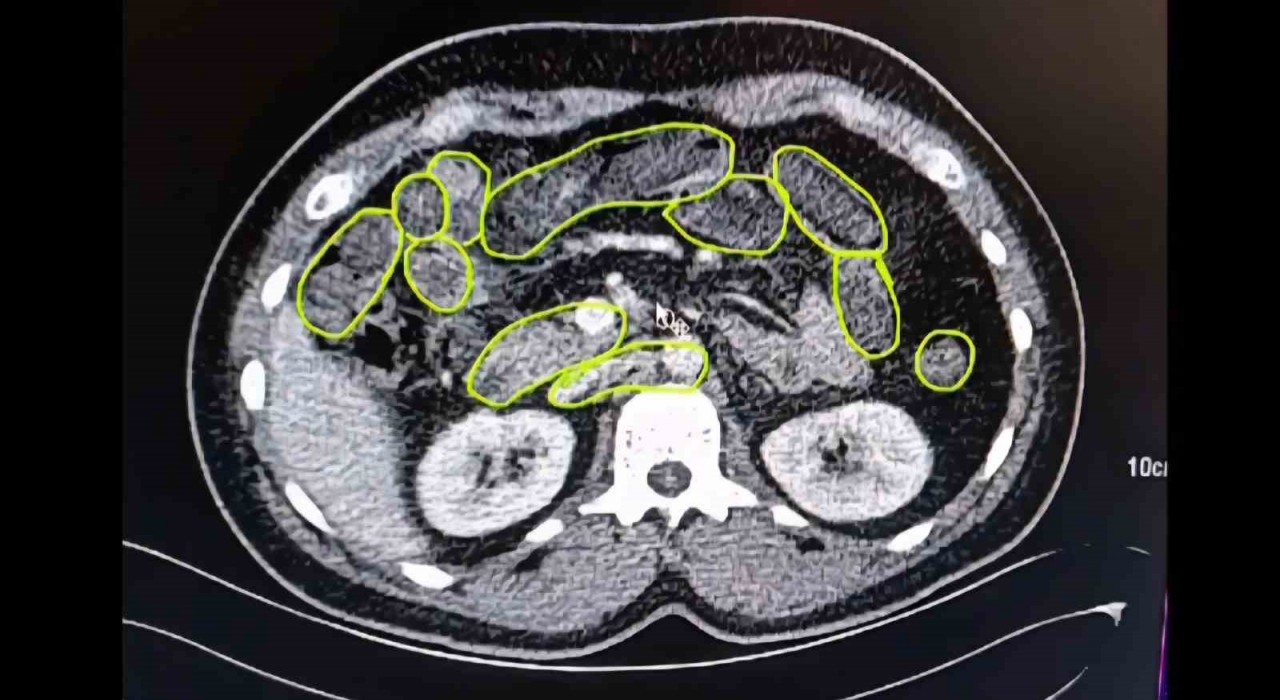

Kayseri'de Jandarma Ekipleri Tarafından Düzenlenen Operasyonda Kente Mide Ve Bağırsaklarında Uyuşturucu Madde Sokmaya çalışan 3 şüpheli Yakalandı.

Kayseri’de jandarma ekipleri tarafından düzenlenen operasyonda kente mide ve bağırsaklarında uyuşturucu madde sokmaya çalışan 3 şüpheli yakalandı.

Edinilen bilgiye göre, İl Jandarma Komutanlığı ekipleri tarafından yapılan çalışmalarda, yabancı uyruklu A.O., M.S. ve P.S.’nin İran’dan temin ettikleri uyuşturucu maddeleri ağızdan yutmak suretiyle mide ve bağırsaklarında gizleyerek kente getireceklerini tespit etti. Şahısların bulunduğu aracı takibe alan ekipler Ankara yolunda aracı durdurdu. Şahıslar gözaltına alınırken, yapılan üst ve eşya aramalarında 20 gram uyuşturucu madde ve 117 adet uyuşturucu hap ele geçirildi.

Şüphelilerin Kayseri Şehir Hastanesinde iç beden muayenesine alınırken, mide ve bağırsaklarında da çok miktarda kapsül şeklinde uyuşturucu olduğu değerlendirilen yabancı maddeler tespit edildi.